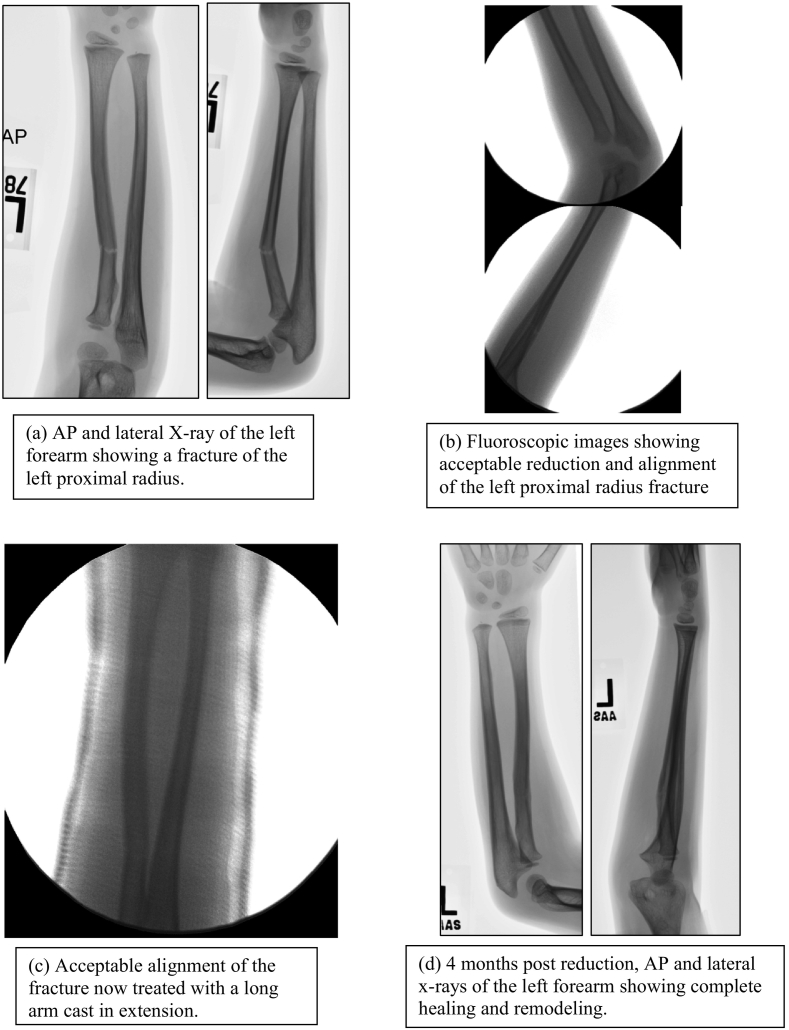

The patient is a right-handed 7-year-old female with a left forearm fracture due to a fall off a trampoline. Radiographs revealed a transverse minimally displaced fracture of the left proximal radius with apex volar and ulna angulation Fig. 2a. The fracture was reduced and subsequently treated in a long arm cast in extension.

Fig. 2.

Radiographic images showing a fracture of the left proximal radius, closed reduced and casted in extension.

The fracture was reduced and parallel alignment of the radius and ulna were confirmed with the fluoroscopy Fig. 2b. The arm was also noted to be clinically straight. A well-molded and well-padded long arm cast was then applied with the elbow in extension Fig. 2c. The cast was placed in supination and a flat interosseous and humerus mold was applied. General casting techniques are maintained for a long arm extension cast. Some unique considerations include applying benzoin to the edge of stockinette at the proximal end of the cast to prevent slippage, and applying a supracondylar mold to the cast for the same purpose. Some orthopaedists have also anecdotally recommended including the thumb in the cast to reduce slippage of the cast. Demonstration of effective casting technique is shown in Fig. 3. Some additional pearls for casting in extension include the use plaster in an acute setting with fiberglass over the top and use of fluoroscopy to confirm adequate reduction has been obtained.

The cast was taken down after 5 weeks, radiographs showed good callus formation as well as anatomic alignment. At 4 months after injury (Fig. 2d), radiographs showed complete healing and remodeling of the forearm fracture with the bones in parallel alignment. Thereafter, she was discharged with no activity restrictions.